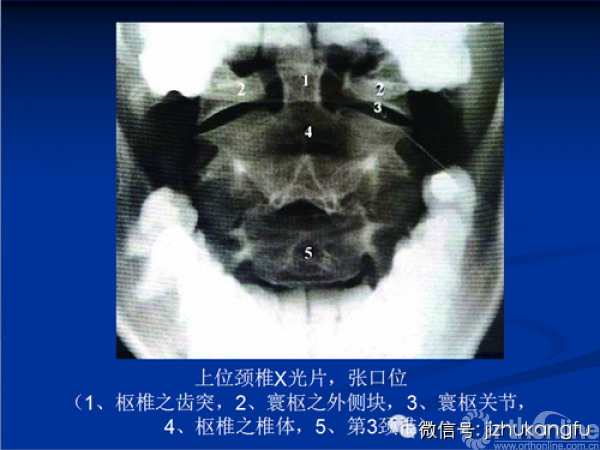

1寰枢椎的判读